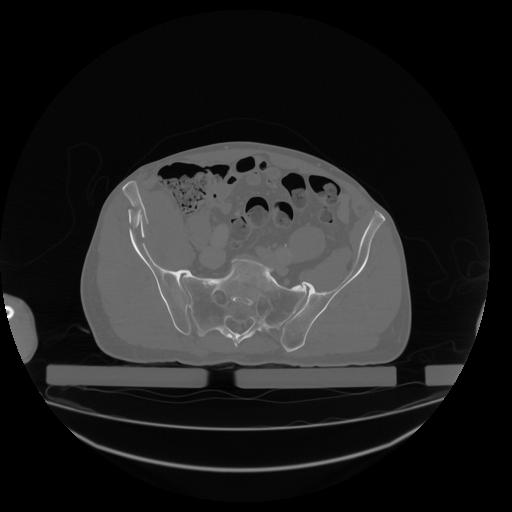

34 CUERPO,CE,Vol,1.0,CUERPO,,